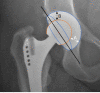

Methods: This observational prospective single-center cohort study with a 10-year follow-up includes a documented series of elective THAs. Primary outcome was wear measured by anteroposterior (AP) radiographs. Secondary outcomes were potential predictive factors for wear, complications during follow-up, Harris hip score (HHS), and radiological findings such as presence of radiolucency, osteolysis, atrophy, and hypertrophy around the cup. Due to the absence of wear in the CoC group, stratified analysis to identify risk factors for wear was only performed in the CoPE group by use of univariate linear regression analysis. HHS was expressed as a change from baseline and the association with bearing type was assessed by use of multivariate linear regression analysis, adjusted for potential confounders.

Results: A total of 17 CoPE (63.0%) and 25 CoC (73.5%) cases were available for follow-up and showed a linear wear of respectively 0.130 mm/year (range 0.010; 0.350) and 0.000 mm/year (range 0.000; 0.005), which was significant (P < 0.001) between both groups. Wear always occurred in the cranial direction. Cup inclination was the only predictive factor for polyethylene (PE) wear. No dislocations, ceramic head, or liner fractures were seen. The HHS showed a mean change from baseline of 37.1 points (SD 18.5) in the CoPE group and 43.9 (SD 17.0) in the CoC group. This crude difference of 6.8 (range -5.2; 18.7) in favor of the CoC group was not significant (P = 0.26) and was not significant when adjusted for age, gender, and diagnosis either (P = 0.99). No significant differences in complications and radiological findings were seen between groups.